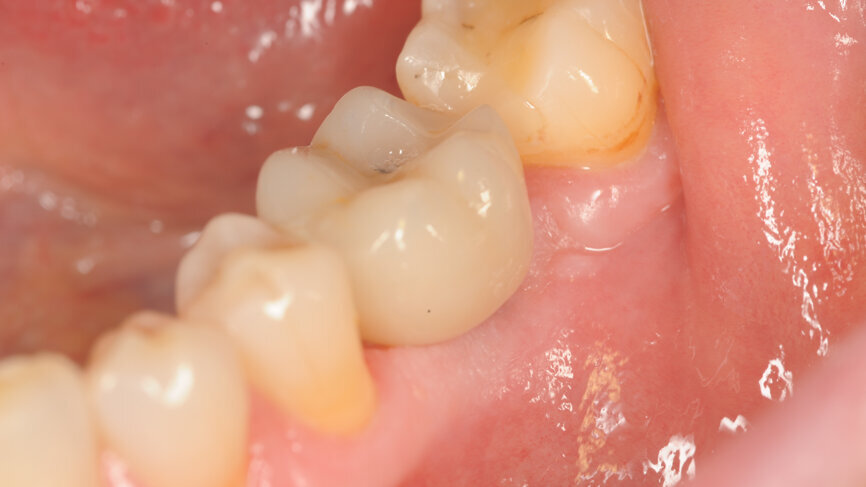

A BLT implant (Regular Neck, Roxolid, ⌀ 4.1 × 12.0 mm) was placed in position #15. As the insertion torque value and Implant Stability Quotient (ISQ) level were not optimal for immediate loading, a delayed protocol with a healing cap was selected.

Two months later, a panoramic radiograph showed an excellent situation for the BLT implant and correct healing of position #36 (Fig. 1). Following a chairside protocol, it was decided to load implant #15 and provide an implant treatment with immediate loading in position #36 on the same day. This involved the design of two screw-retained crowns with the TRIOS Design Studio software, and their production in n!ce material on the C series milling unit.